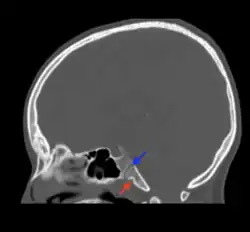

Fosas navicularis magna (red arrow) on mid-sagittal computed tomography

Fossa navicularis magna (also known as pharyngeal fossa or phyaryngeal fovela) is a variant bony depression found at the midline of the occipital part of clivus. This fossa was first described by Tourtual.[1] Its prevalence ranges from 0.9 to 5.3%.[2]

Fossa navicularis magna is located on the anterior surface or pharyngeal surface of the clivus. Its position when present is between the spheno-occipital synchondrosis and the foramen magnum. Size of this fossa varies considerably and its depth ranges from 3.49 to 4.94 mm.[3] A histological study reported the presence of loose connective tissue containing collagen and elastic fibers within the fossa navicularis magna.[4]